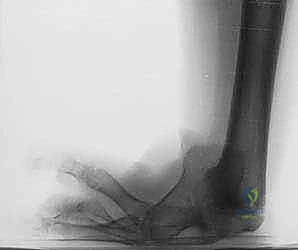

المرحلة الأولى: التخطيط ما قبل الجراحة

تبدأ الرحلة بتقييم شعاعي دقيق (أشعة سينية، وأحياناً رنين مغناطيسي MRI لتقييم الأربطة). يتم قياس التفاوت في طول الأطراف بدقة، وتحديد زوايا الانحراف. يجلس الدكتور هطيف مع العائلة في جلسة استشارية مطولة، يشرح فيها كل التفاصيل، ويجيب على كافة التساؤلات بأمانة طبية مطلقة، مما يزرع الطمأنينة في قلوب الآباء.